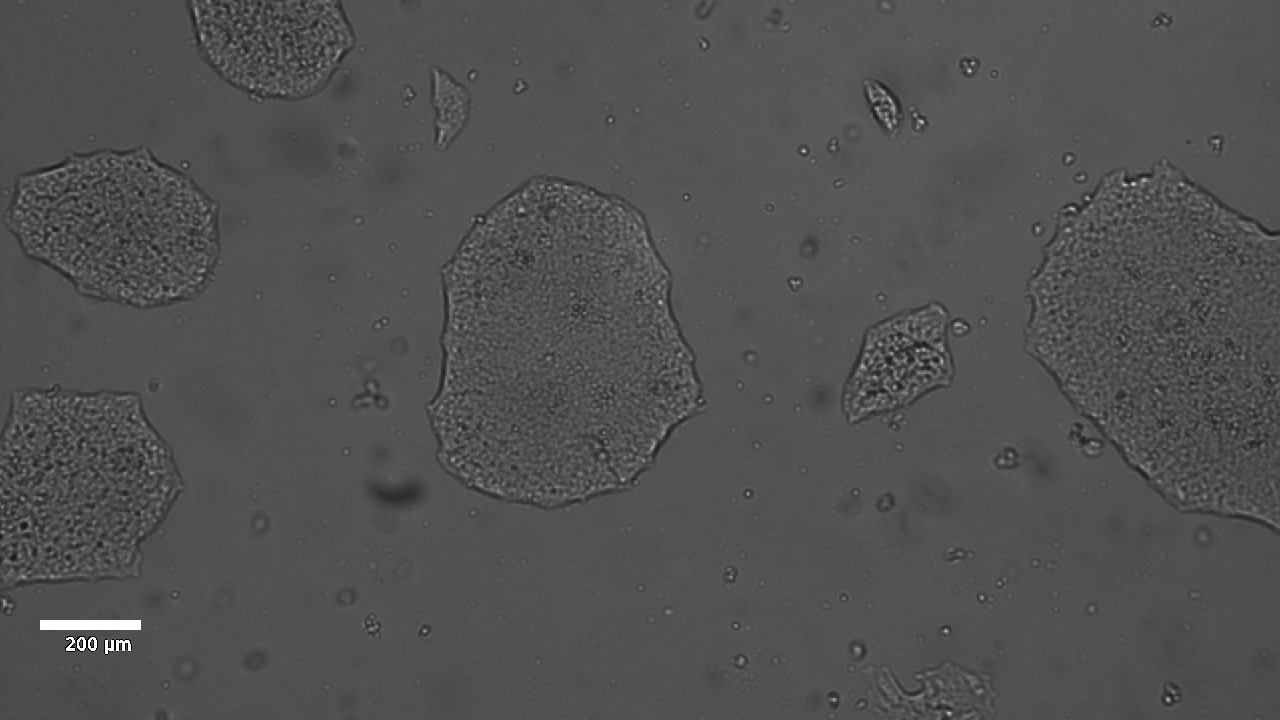

Analysis of Undifferentiated Cells

| Marker | Expressed | Immunostaining | RT-PCR | Flow Cytometry | Enzymatic Assay | Expression Profiles |

| POU5F1 (OCT-4) |

Yes |

|||||

| TRA 1-60 |

| SOX2 |

| SSEA-4 |